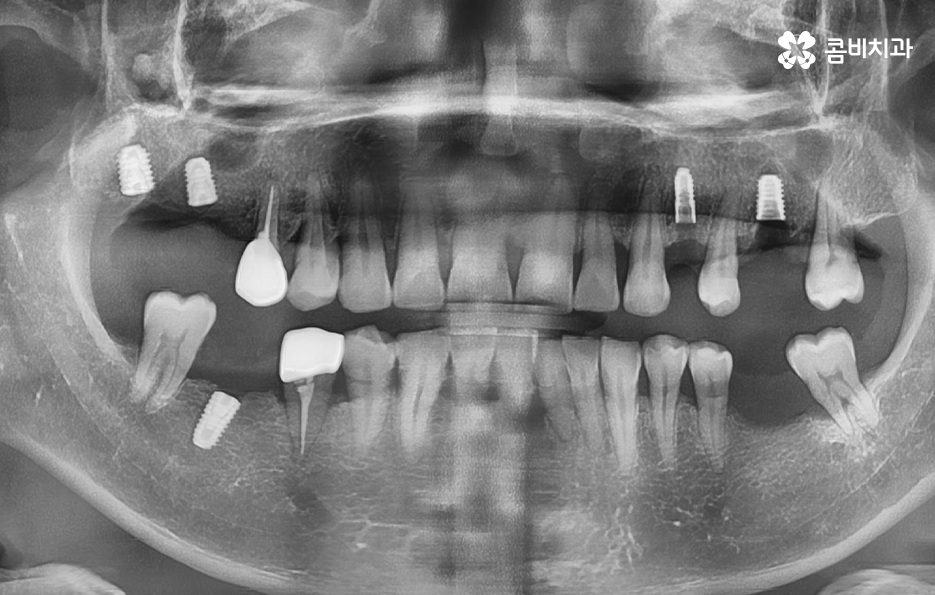

위 케이스의 노인임플란트 치료의 경우 치아의 균열부터 뿌리까지 깊어진 충치, 치주염 까지 복합적인 이유로 치아를 상실하고 여러 개의 임플란트를 식립한 사례라고 할 수 있는데요. 그래도 아직은 잔존하고 있는 치아가 많기 때문에 이미 상실한 치아에는 노인임플란트 각 위치에 맞게 적절한 치료를 받고 나머지의 자연치아에 대해서는 잘 관리하는 것이 중요한 시점이라 할 수 있어요

위 환자분의 케이스는 대부분 어금니 위주로 상실하여 노인임플란트 적절하게 식립하여 어금니의 저작기능을 수복했는데요. 노인임플란트 하면 건강보험에 대한 적용이나 저렴한 치료 비용에 대한 관심을 갖는 경우가 많긴 하지만 연령대에 따라 치아의 잔존율이 크게 급감하는 원인에 대해 잘 알아두시고 이제 치아를 하나 둘씩 잃기 시작했다면 이 시기부터 보다 적극적으로 자연치아를 보존하는 방법을 잘 숙지하시고 특히 주기적으로 치과 검진과 스케일링을 생활화 하는 것이 강조되고 있어요